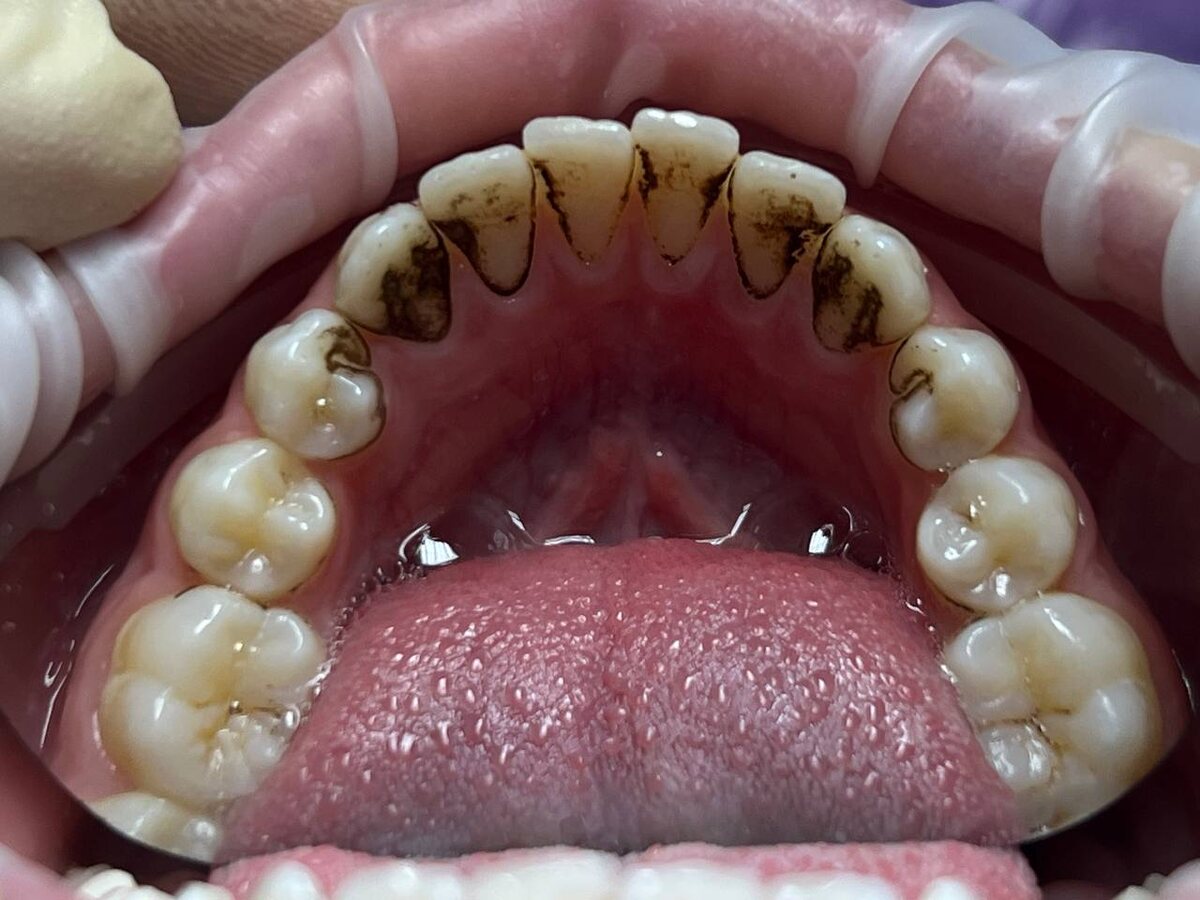

Налет Присли представляет собой специфическую форму зубного налета, которая чаще всего заметна у детей. Его описание включает несколько ключевых характеристик:

- Плотная и темная текстура, колеблющаяся от коричневого до почти черного оттенка;

- Чаще всего располагается вдоль линии десен и на внешней поверхности зубов;

- Не поддается очистке с помощью обычной зубной щетки и пасты;

- Несмотря на наличие налета, зубы могут оставаться в полностью здоровом состоянии, что, однако, создаст эстетический дискомфорт.